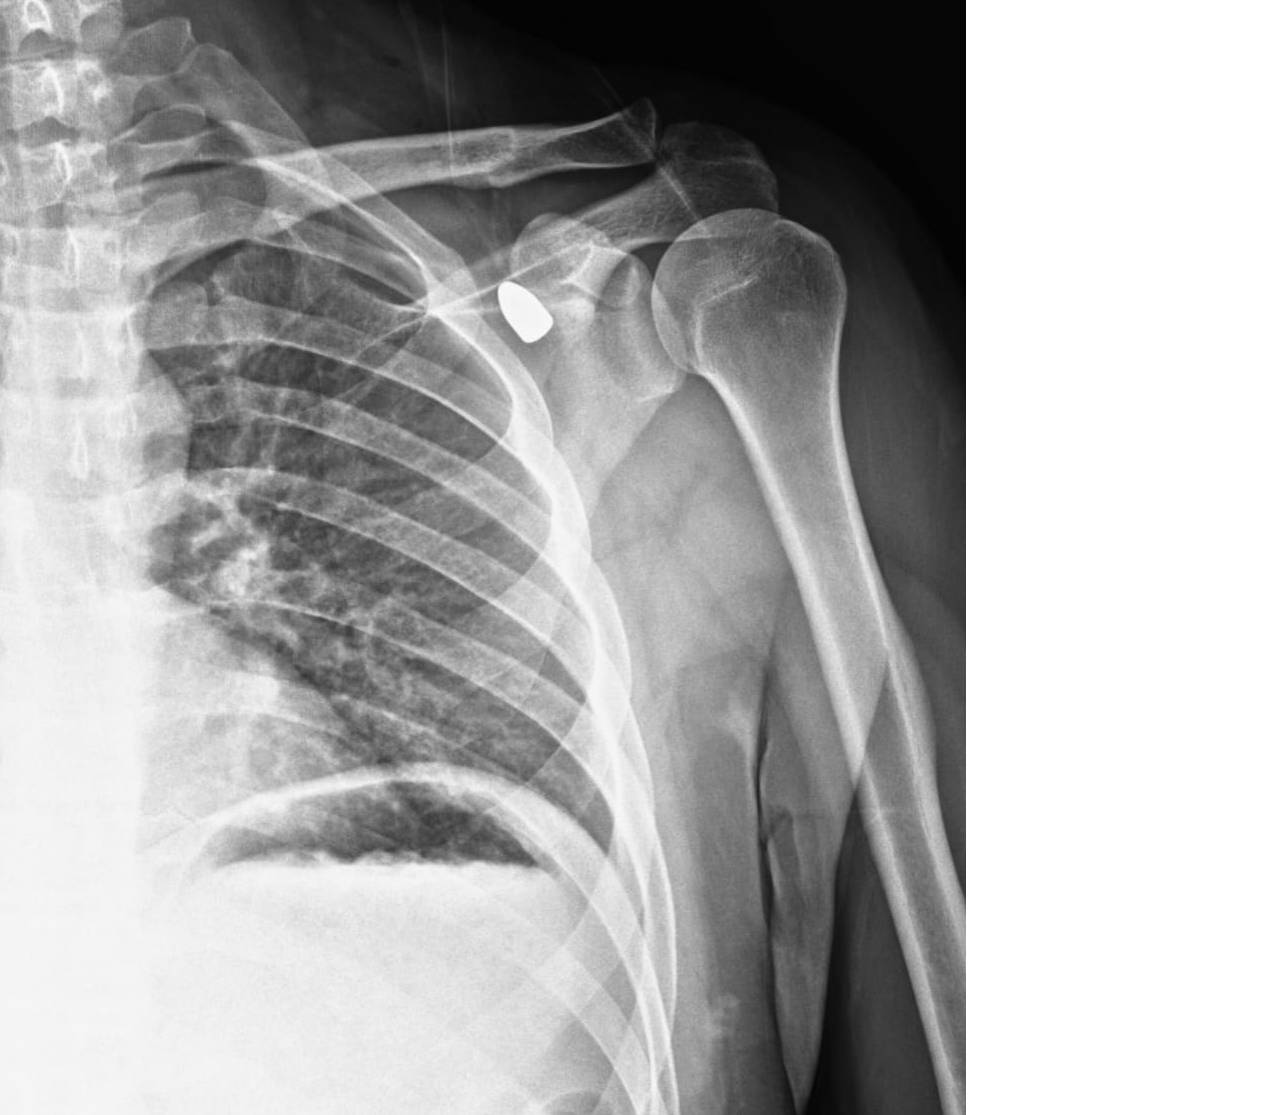

Konya'nın Akşehir ilçesinde altı yıl önce bir okul müdürünün omzuna isabet eden yorgun mermi tıbbi müdahaleyle çıkarıldı. Okul müdürü Celal Şenyiğit, Adsız Mahallesi'ndeki çay ocağında, altı yıl önce omzuna isabet eden yorgun mermiyle yaralandı.

Hareket kaybı riski nedeniyle çıkarılamayan mermi, zamanla Şenyiğit'in koltuk altına ilerledi. Ağrı ve sertlik şikayetiyle Akşehir Devlet Hastanesine başvuran Şenyiğit'in koltuk altındaki kitlenin, omzuna saplanan yorgun mermi olduğu tespit edildi.

Mermi, gerçekleştirilen operasyonla çıkarıldı. Şenyiğit, olayla ilgili şikayetçi olduğunu, çıkarılan merminin incelemeye gönderildiğini söyledi.